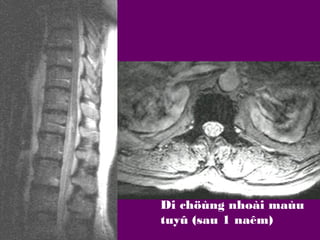

Nhoài

Di chöùng nhoài maùu

tuyû (sau 1 naêm)